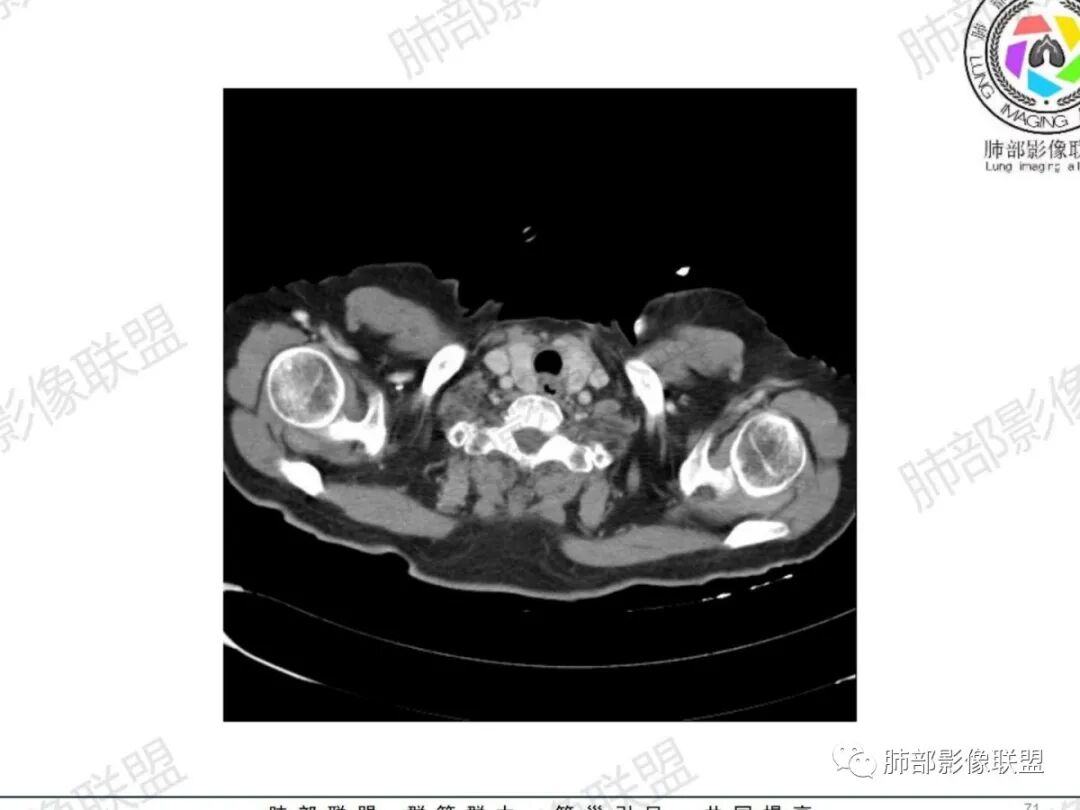

从病史提示:甲状腺占位、气管占位、肺部炎症

左肺下叶背段见树芽征

甲状腺左叶结节边界不太清楚

气管右后壁占位,平扫密度稍低于肌肉

甲状腺结节边界不太清楚,但是窗宽窗位不太理想,需要调至最佳状态观察才合适

病理类型:甲状腺如果是恶性的,还是要警惕转移瘤;原发的:倾向于恶性,老年女性,表面光滑, 鳞癌几率比较低;腺样囊性癌确实要考虑